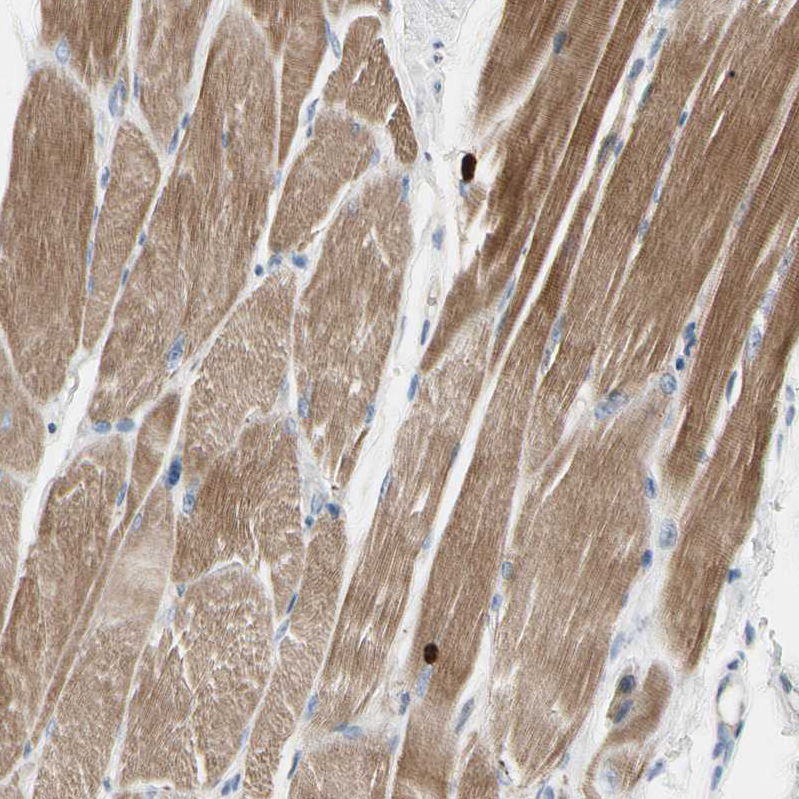

Immunohistochemical staining of human skeletal muscle shows moderate cytoplasmic positivity in myocytes.